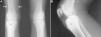

A 15-year-old boy presented with an 8-month history of mechanical pain in right knee. It would be intermittent at first and later become continuous, making it difficult for him to walk, and swelling was observed in that area. The treatment consisted of nonsteroidal anti-inflammatory drugs (NSAID), initially ibuprofen, which was replaced by diclofenac, but there was no improvement. He had no history of injury, fever or constitutional symptoms, or manifestations affecting any other peripheral or axial joint or enthesitis. He had been diagnosed with guttate psoriasis at the age of 10 years, with occasional episodes until he was 13, and was treated with topical glucocorticoids; however, he had no family history of psoriasis, psoriatic arthritis, ankylosing spondylitis or inflammatory bowel disease. Physical examination revealed muscle atrophy in distal thigh and swelling in right infrapatellar region, which was warm, and he had a limitation in last few degrees of flexion, but with no signs of joint effusion. The results of laboratory tests, including biochemical analyses, complete blood count and acute-phase reactants (erythrocyte sedimentation rate 6mm/h, C-reactive protein 2.31mg/dL) were normal. Human leukocyte antigen (HLA) typing revealed the presence of Cw6, DR4 and DQ8 haplotypes, but not B27, and the patient was negative for rheumatoid factor and antinuclear antibodies. Plain radiography of the knees showed a sclerotic area in the upper third of right tibia (Fig. 1A and B), which, according to computed tomography (CT), corresponded to an osteolytic lesion measuring 5mm in diameter in anterior tibial tuberosity, with a “nidus” formed by an ossified matrix, compatible with OO (Fig. 2B and C), with extensive sclerosis of the medullary bone and a solid periosteal reaction in the adjacent cortical bone. Magnetic resonance revealed intense contrast uptake in and around the lesion, as well as in the surrounding bone edema and the Hoffa fat pad (Fig. 2C and D). Bone scintigraphy disclosed hyperemia and a focal increase in the osteogenic response in the proximal epiphysis of right tibia, with no other significant changes. The patient underwent CT-guided radiofrequency ablation, and the pain disappeared a few days after the procedure, and he recovered complete mobility 1 month later, although he had mild persistent muscle atrophy.